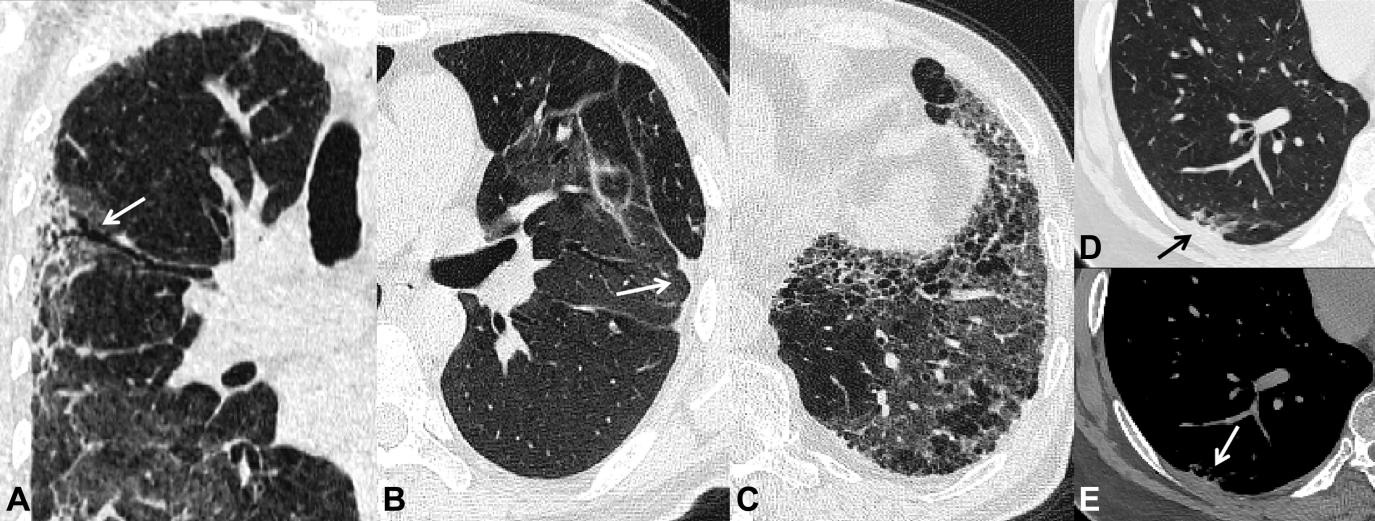

Những di chứng sau viêm phổi do SARS-COV2 được ghi nhận trên phim CTscan ngực sau 6 tháng theo dõi. A-dãn phế quản co kéo (mũi tên). B- xẹp phổi dạng đường (mũi tên). C- xơ phổi dạng tổ ong. D và E- dày màng phổi tạng (mũi tên)